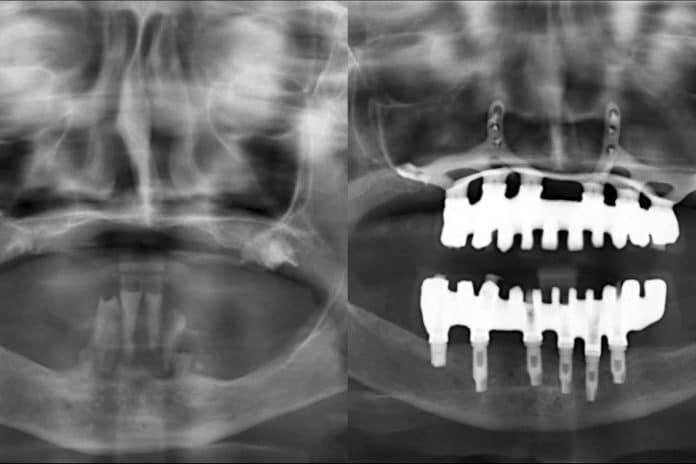

Por otro lado, los cirujanos comenzarán haciéndose una planificación digital y la elección de los materiales regenerativos que mejor se adapten al paciente. Para alcanzar el diagnóstico más preciso, la clínica utiliza tecnología 3D de escáner, con el fin de confeccionar prótesis personalizadas, que pueden ser colocadas en una única intervención.

Concretamente, un implante dental es un tornillo fabricado en titanio que se inserta en el hueso maxilar con el fin de sustituir a la raíz del diente que falta.

En los casos más complejos en los que falta la cantidad de hueso ideal, la técnica del injerto óseo es la indicada, al colocar tejido autólogo, tomado del propio paciente; o heterólogo, de otra especie, por lo general la bovina, para contar con un buen soporte del implante, sin rechazo ni reacciones alérgicas. Sin embargo, otros procedimientos que ofrece la clínica son los implantes corticales en caso de atrofia ósea extrema, los implantes cigomáticos y la técnica de elevación de seno maxilar.

Con muchas de estas técnicas se puede recurrir a la carga inmediata, es decir, colocar la prótesis fija pero provisional sobre estos implantes recién colocados.